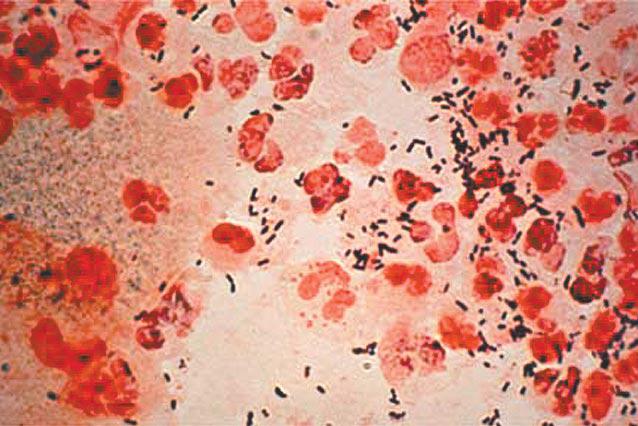

據悉,按摩女郎所患的性病中,其中梅毒對人體的危害僅次於愛滋病。梅毒是由梅毒螺旋體引起,早期侵犯生殖器和皮膚,晚期侵犯全身各器官,並生多種多樣的症狀和體徵,病變幾乎能累及全身各個器官。